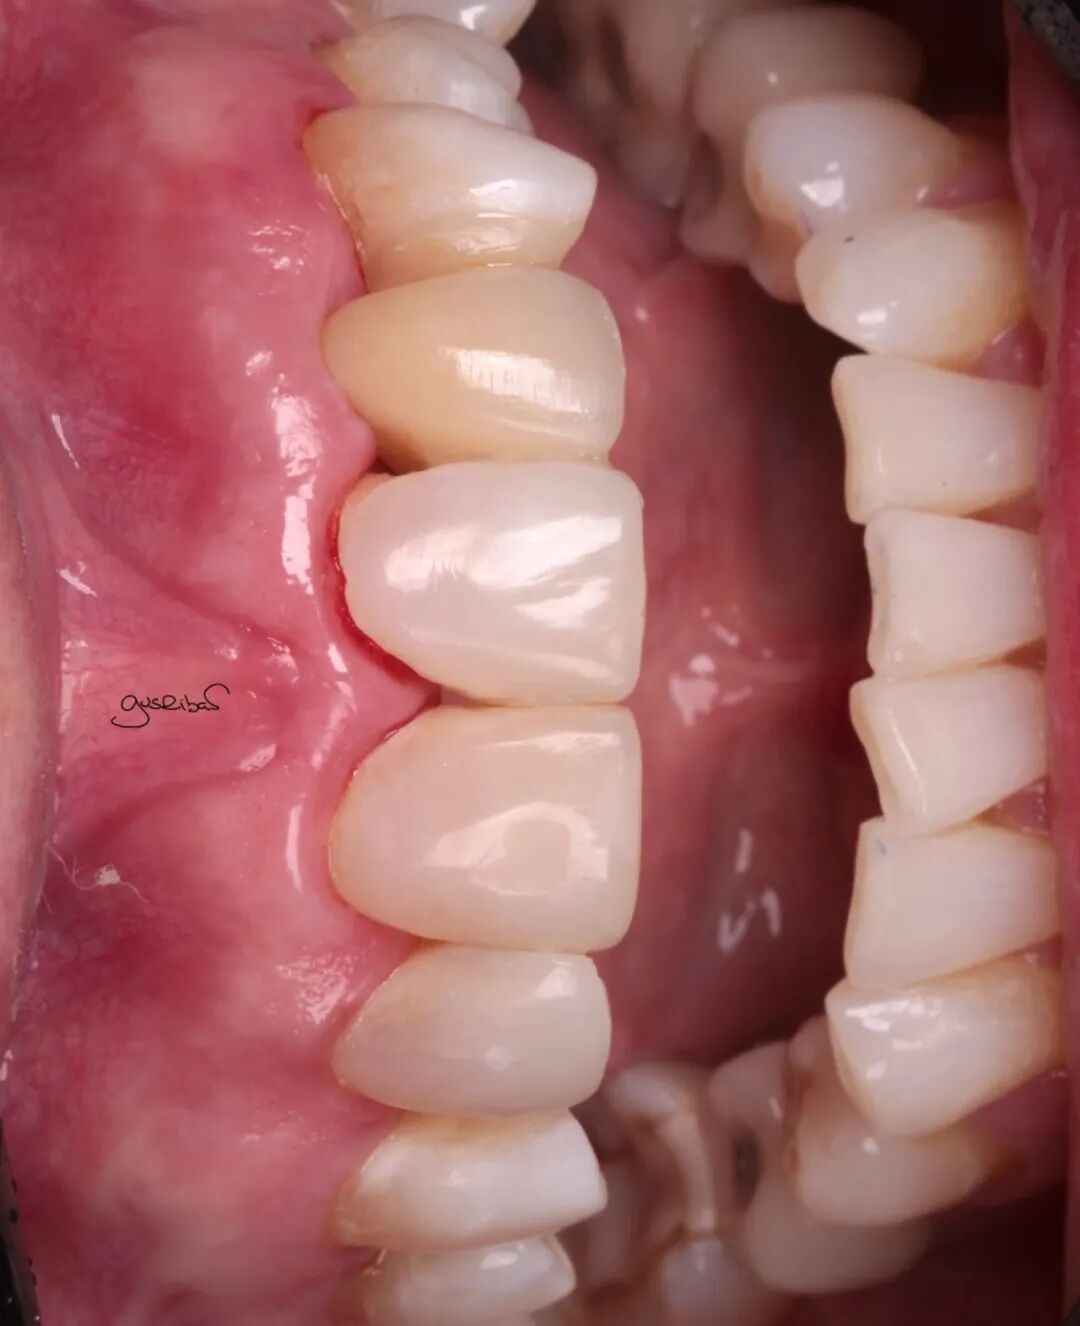

在邻牙上做了部分预备,立即封闭了暴露的牙本质,进行了数字化扫描,完成修复体的制作和美学调整,并用复合树脂进行了粘接。